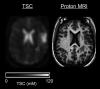

Sodium MR imaging has the potential to complement routine proton MR imaging examinations with the goal of improving diagnosis, disease characterization, and clinical monitoring in neurologic diseases. In the past, the utility and exploration of sodium MR imaging as a valuable clinical tool have been limited due to the extremely low MR signal, but with recent improvements in imaging techniques and hardware, sodium MR imaging is on the verge of becoming clinically realistic for conditions that include brain tumors, ischemic stroke, and epilepsy. In this review, we briefly describe the fundamental physics of sodium MR imaging tailored to the neuroradiologist, focusing on the basics necessary to understand factors that play into making sodium MR imaging feasible for clinical settings and describing current controversies in the field. We will also discuss the current state of the field and the potential future clinical uses of sodium MR imaging in the diagnosis, phenotyping, and therapeutic monitoring in neurologic diseases.